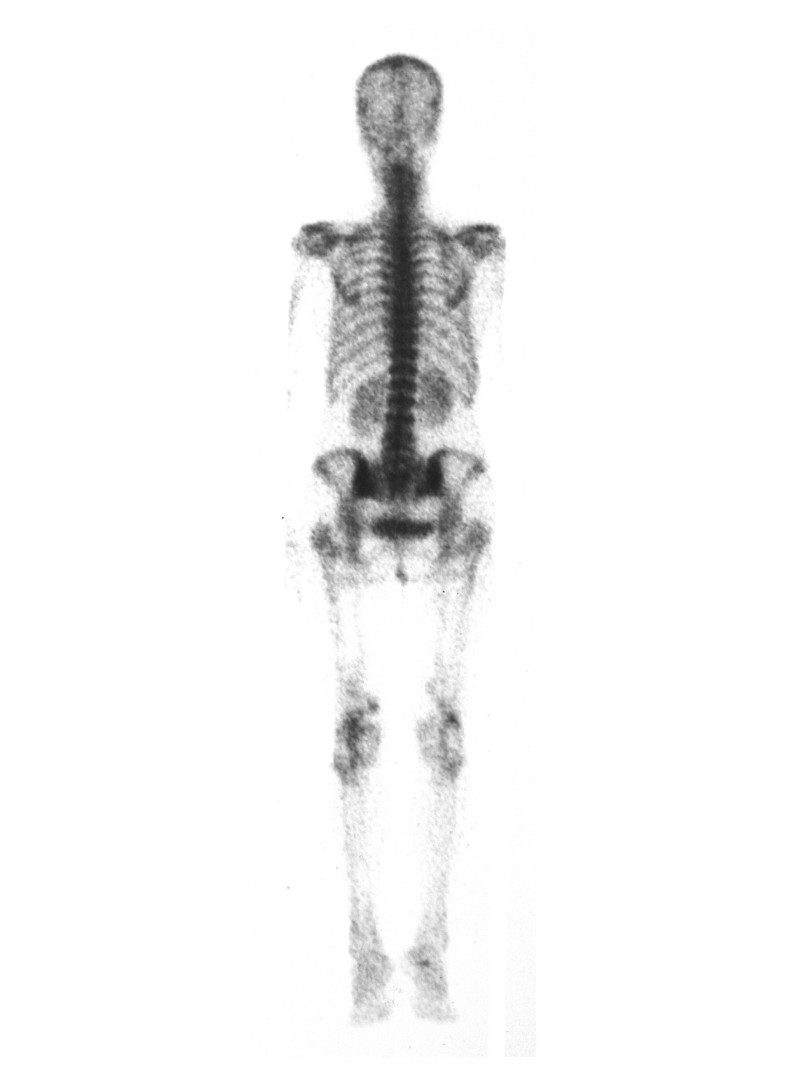

La diagnosi è solitamente incidentale e può avvenire in seguito a una radiografia eseguita per altri motivi, durante l'esame autoptico o durante indagini svolte per diabete mellito o malattia renale cronica. Tipicamente le calcificazioni si osservano nelle arterie degli arti, ma possono essere prenti in numerose altre arterie di medio calibro. Le arterie radiale o ulnare possono presentarsi nella forma detta "a cannello di pipa", in cui il polso è palpabile solamente alla termine dell'area calcifica oppure con completa assenza di polso. Sulla base di studi epidemiologici si è arrivati a definire, come criterio diagnostico per la sclerosi calcifica mediale di Mönckeberg, la presenza di un indice caviglia-braccio superiore a 1,3 o 1,5 a seconda dello studio preso in considerazione.